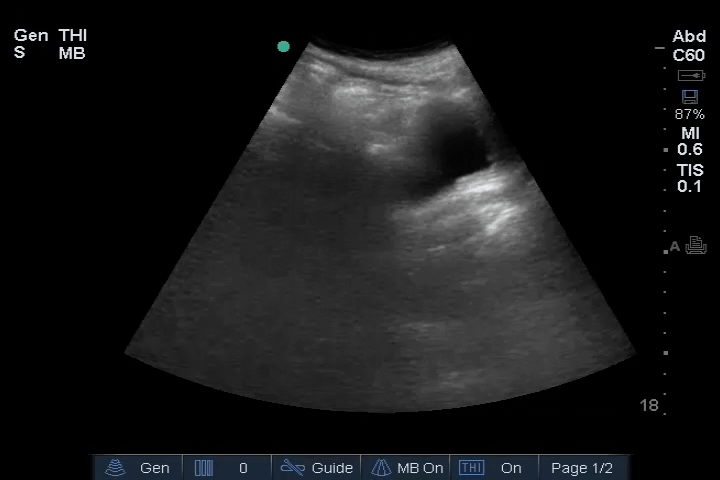

20_Abdomen_RUQ_Perihepatic – Normal

Abdomen: Normal – no free fluid.